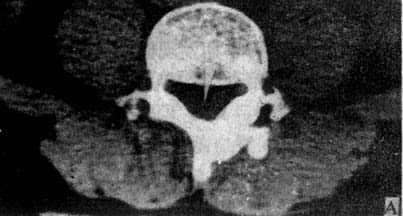

1.椎弓根层面 由椎体、椎弓根、椎弓板棘突围成一完整的骨环称为椎管(图5-1-5A)。正常椎管前后径为16~17mm,下限11.5mm;横径20~24mm,下限16mm。

正常脊柱CT横断面扫描

图5-1-5 正常脊柱CT横断面扫描

A.椎弓根层面显示椎管由椎体、椎弓根和椎弓板围成的骨环,椎管中央为脊髓(→)